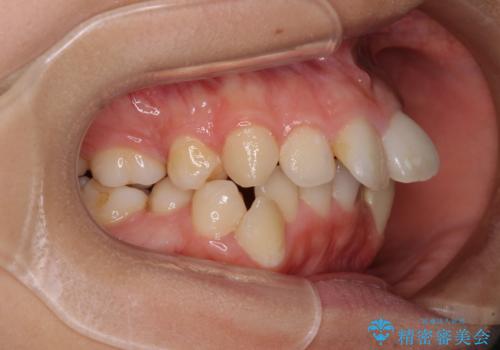

上顎は歯列不正が強く、右側臼歯部の咬み合わせは歯1本分ずれている状態でした。

補助装置を用いて奥歯の咬み合わせを改善しながら歯列を後方に移動させ、上下左右第一小臼歯を4本抜歯することで八重歯や口元の突出感を改善することとしました。

奥歯の咬み合わせの不正が顕著であったため、表側のワイヤー装置を選択して矯正治療を行うこととしました。